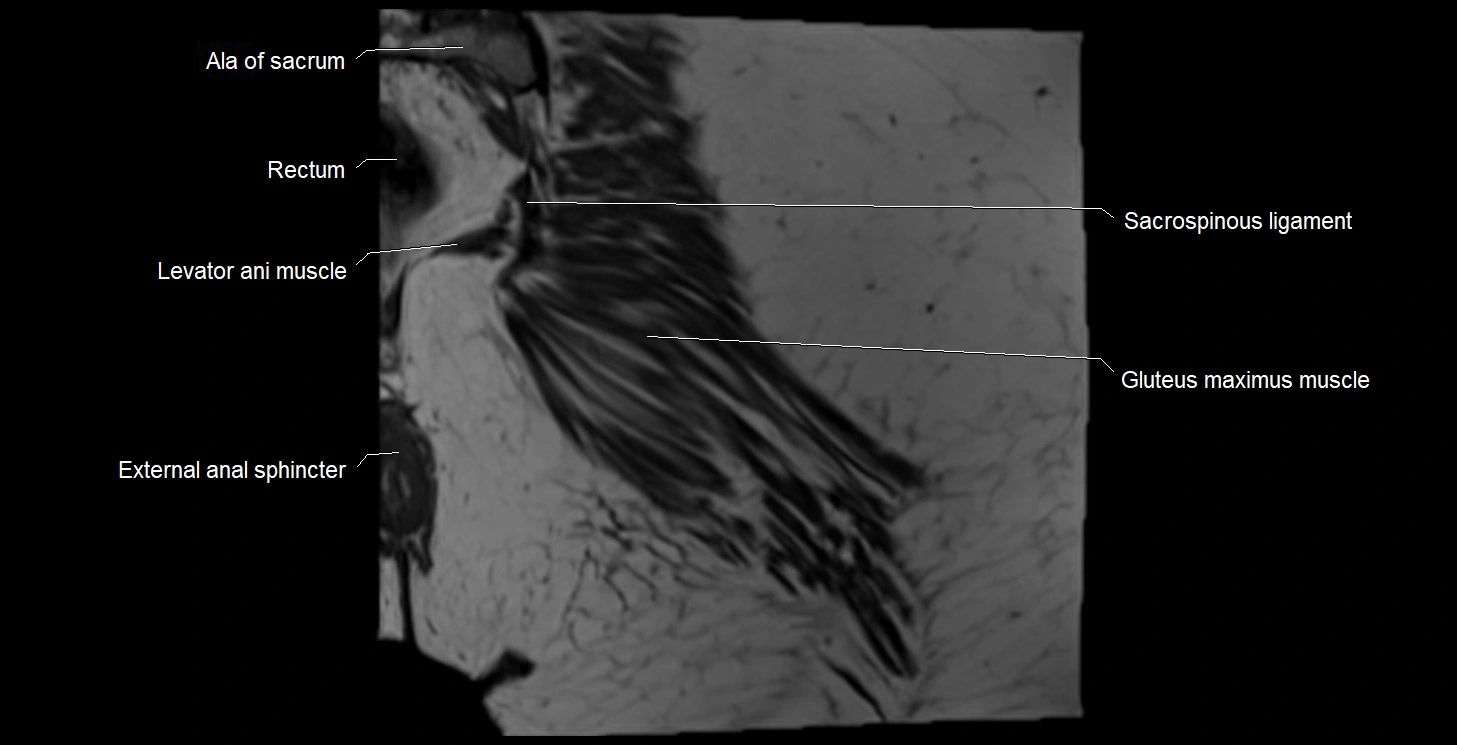

- Ala of sacrum

- External anal sphincter

- Gluteus maximus muscle

- Levator ani muscle

- Rectum

- Sacrospinous ligament